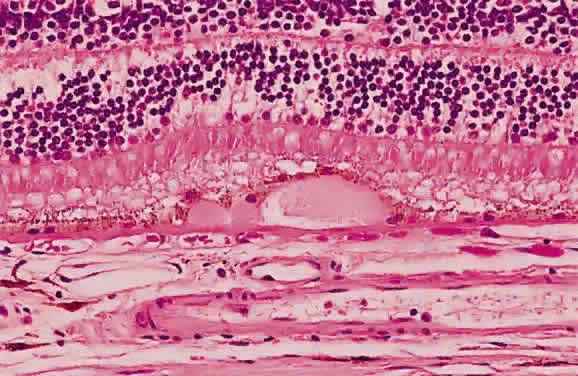

Necrotic retina has a white appearance. Necrosis may result from a variety of inflammatory conditions, including viral, fungal, and protozoal (Toxoplasma) retinitis. Each type of retinitis appears, in part, as a white retinal lesion. Cytomegalovirus retinitis (Fig. 24) resembles a pizza pie with an admixture of white (retinal inflammation) and red (hemorrhage) colors (Fig. 25). The retinal abscesses of fungal retinitis are white. Likewise, the satellite lesion of retinochoroiditis caused by active Toxoplasma (the choroidal inflammation is merely in response to the primary retinal infection) is white (Fig. 26). The white appearance of a lesion from inactive Toxoplasma results from the destruction of neurosensory retina, retinal pigment epithelium, and choroid to permit a direct view of the sclera (Fig. 27). Necrosis in retinal-derived neoplasms is white; the appearance of regressed (necrotic) retinoblastoma often is described as “cottage cheese.”10

Fig. 24. A. Histologic section of cytomegalic inclusion retinitis. The characteristic inclusions cannot be seen at this magnification. Compare the appearance of viable healthy retina (left of arrow) with necrotic retina (right of arrow). The admixture of necrotic retina (clinically white) with hemorrhage (clinically red) accounts for the ophthalmoscopic appearance of this entity. B. Cytomegalovirus retinitis. Histologic section of sensory retina demonstrating massive necrosis involving all layers. (Courtesy of Ralph C. Eagle Jr, MD, Philadelphia, PA)